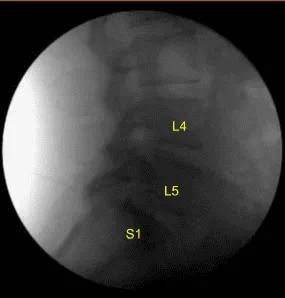

Spinal needle and fluoroscopy were used to localize the L5-S1 level. A midline incision was demarcated. Skin was sterilized with DuraPrep. Sterile drapes were placed in usual manner. 1% lidocaine with epinephrine was infused.

Skin was opened with #10 blade scalpel. Hemostasis was obtained with bipolar. Bovie monopolar and Cobb elevators were used to carry the incision down, incising the fascia and performing subperiosteal dissection exposing the L4, L5 and S1. Self-retaining retractors were placed. A Woodson elevator was placed under the L4 lamina. C-arm unit, which was draped sterilely, was brought into the field and used to confirm the level.

L4, L5 and S1 spinous processes were resected with Horsley rib cutters and Leksell rongeurs. Bone bleeding was controlled with bone wax. Electric high-speed drill with sterile irrigation was used to perform L4, L5 and S1 laminectomy. This was continued with Kerrison rongeurs, carefully protecting the dura. No cerebrospinal fluid or durotomy was identified.

Hypertrophied ligamentum flavum was resected at L4 and L5. Significant epidural lipomatosis similar to preoperative imaging was identified at L5-S1. Lateral recess at L4, L5 and S1 was decompressed with Kerrison rongeurs. Decompression was confirmed with nerve hooks and Woodson elevators. Bilateral L4, L5 and S1 nerve roots were completely neurolyzed with Metzenbaum-Penfield technique and confirmed with nerve hooks.